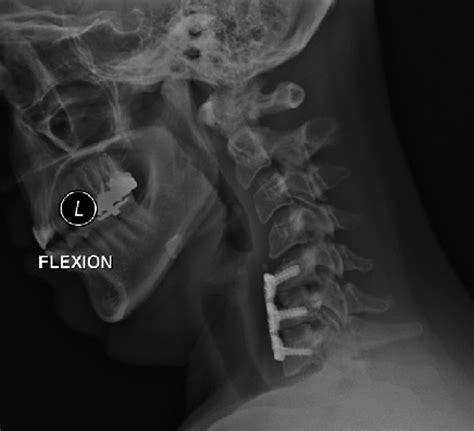

1. Anterior Cervical Discectomy and Fusion (ACDF)

This is the “gold standard” for many neck-related issues. The surgeon accesses the spine from the front of the neck, removes the damaged disc, and replaces it with a bone graft or a cage to allow the vertebrae to fuse over time.

2. Artificial Disc Replacement (ADR)

Unlike fusion, which restricts motion, ADR involves replacing the damaged disc with a prosthetic device. This is often chosen for younger, active patients who wish to maintain as much neck mobility as possible.